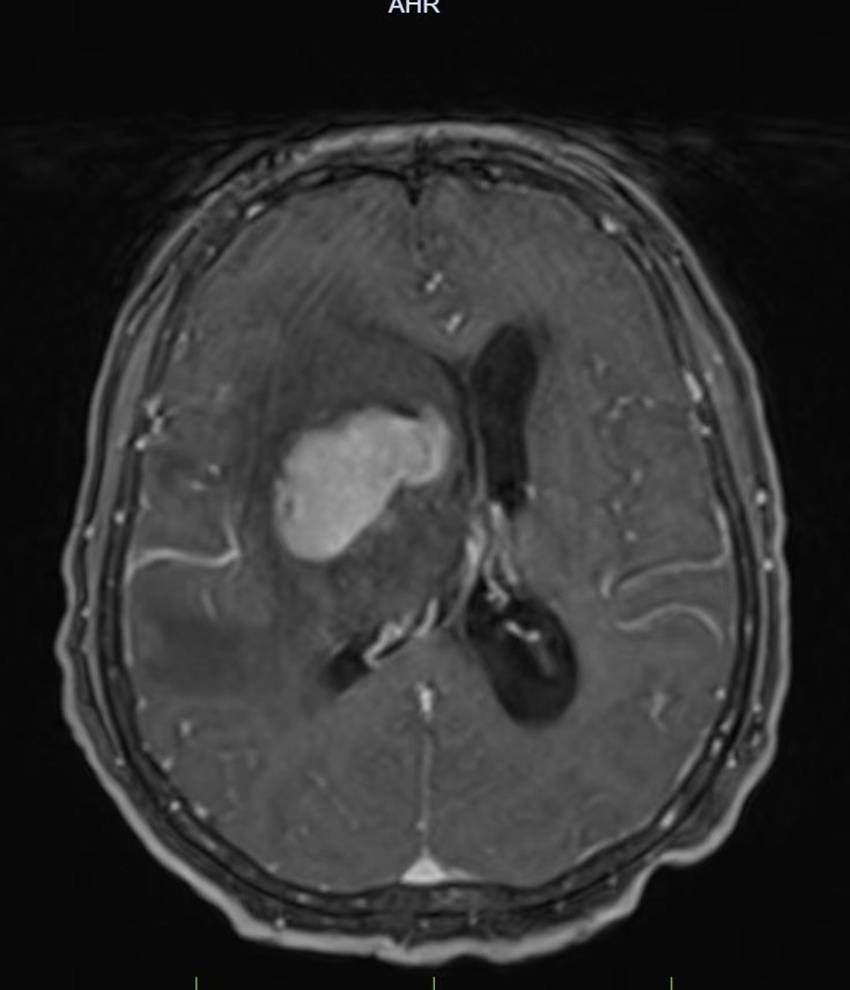

治疗过程中,团队依托3.0T头颅磁共振成像(MRI)精准定位,聚焦病灶区域实施精准放射治疗,最大限度保护正常脑组织,迅速解除神经压迫。同时,同步推进平喘、化痰、抗炎、抗真菌、输血纠正贫血等对症支持治疗,全程密切监测血常规、肝肾功能及电解质水平,确保治疗安全与患者耐受度。

治疗前后病灶对比明显缩小

放疗进行至半程时,复查MRI显示:病灶及周围脑组织水肿范围明显缩小,中线结构完全复位。患者也从最初卧床无法活动,逐步实现搀扶站立,最终平稳独立行走。